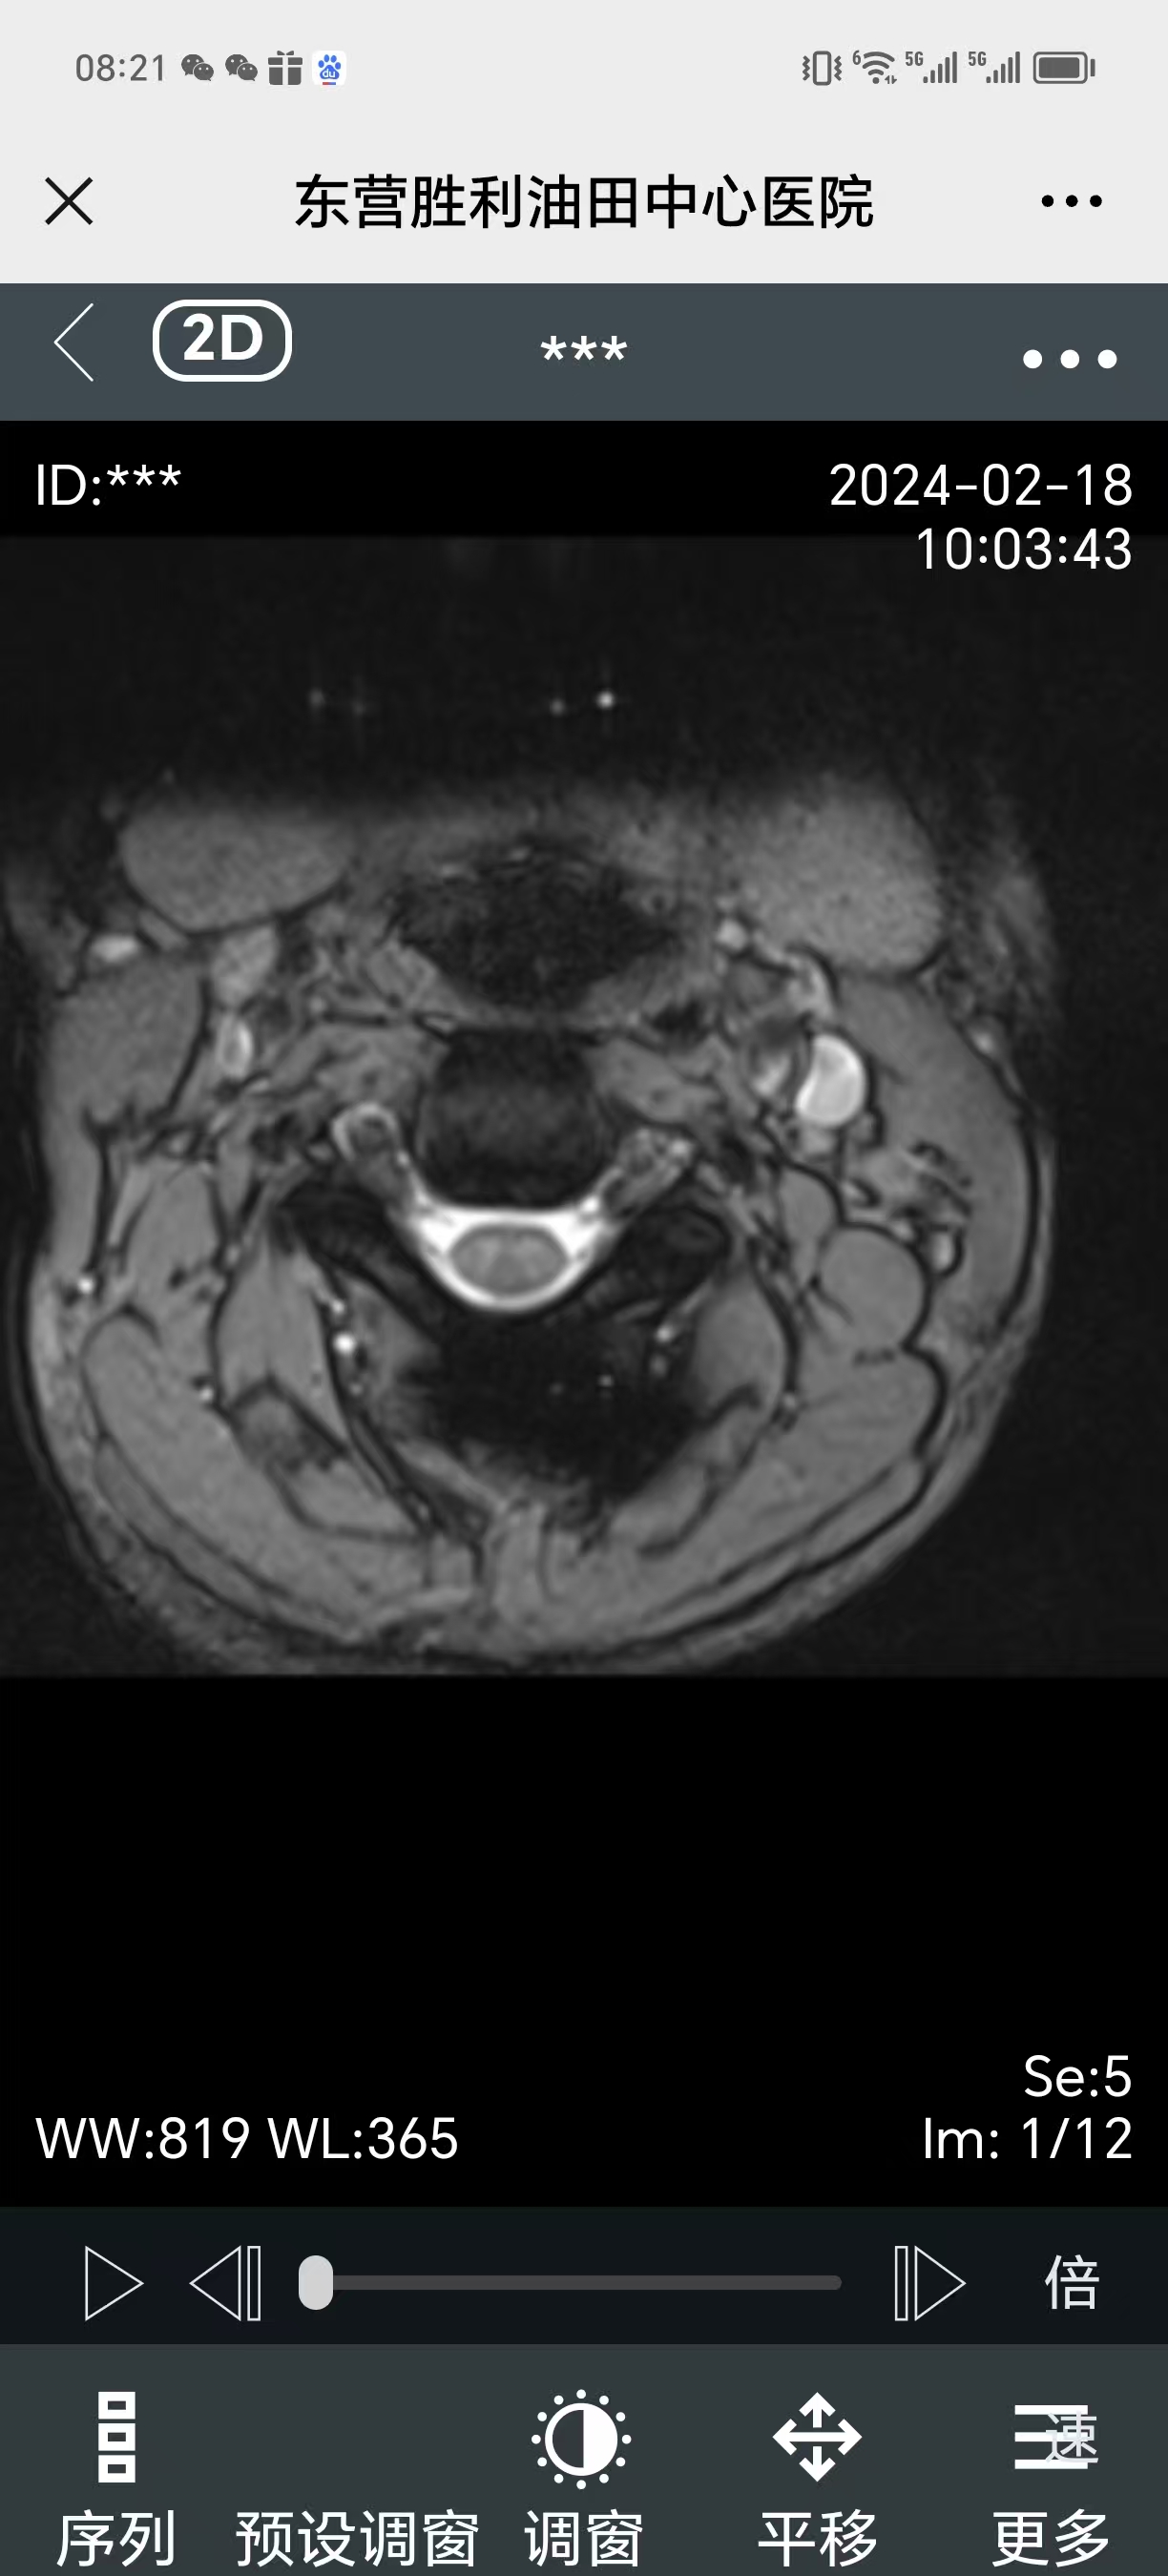

• 2024.02.18,复查,症状还在。